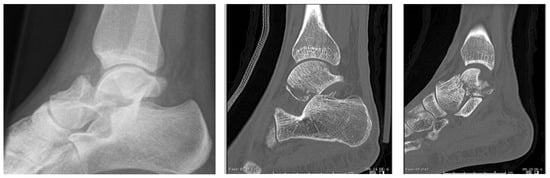

2.1. Surgical Technique